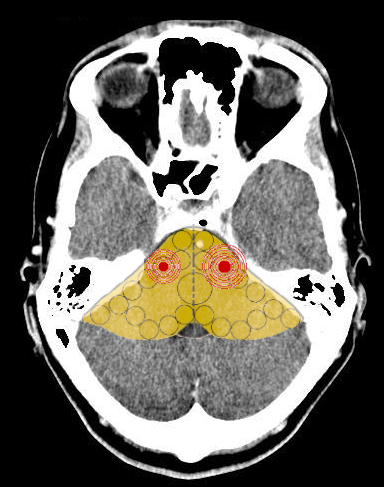

- Relè cerebrali: Due SBS (uno in ogni emitronco cerebrale);

- Relè cerebrali: Due SBS a livello cerebellare